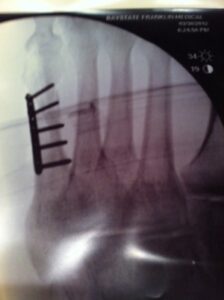

It’s been a solid week since I went under the knife and emerged with five screws, a metal plate and the inability to put any weight on my left foot. I’ve learned what I can and cannot do and the latter dominates the list. It’s the little things that really […]

So now that I’ve had five screws inserted into my fifth metatarsal, I’m settling in here for a long period of ….well, not walking. I got a nice comment from a guy named Bob Hale on my blog who reaffirmed that with a foot injury, there is really only one […]

A Foot Operation Gives Me Empathy for Those More Familiar with Hospitals

Yesterday I had a visit with the orthopedist who is looking after my broken foot. I had hoped that the X-ray would show a good pattern of bone growth, that seven days would give that metatarsal a chance to close up and heal. But when we looked at the new […]